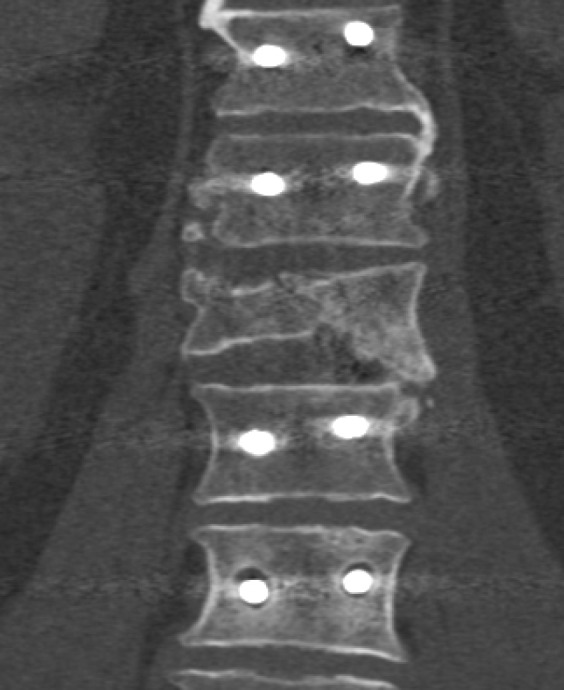

Methods: This study is a non-randomized single center ambispective evaluation of 204 consecutive patients (117 men; 87 women) with unstable thoracolumbar injuries. All patients underwent either stand-alone or combined with anterior column reconstruction instrumentation. In cases with spinal cord and nerve root injuries, either posterior or anterior decompression were performed. Patients with pedicle screw loosening were identified via computed tomography imaging. Out of those, cases with clinically significant instrumentation failure were registered.

Results: The rate of pedicle screw loosening detected by computed tomography was inversely correlated with bone radiodensity figures and an increased association with the number of instrumented levels, residual kyphotic deformity, laminectomy, and lumbosacral fixation. Intermediate screws and anterior reconstruction were associated with a clinically relevant decreased risk of pedicle screw loosening development. Either complete or partial posterior fusion within instrumented levels was capable of decreasing instrumentation failure risk, while extensive decompression with laminectomy and at least one-level total facetectomy were associated with an increased risk of instrumentation failure. Anterior decompression does not have a negative impact on instrumentation stability.

Conclusion: Intermediate screws, anterior reconstruction and posterior tension band preservation are associated with decreased rates of instrumentation instability development. Posterior fusion is beneficial in terms of instrumentation failure prevention.